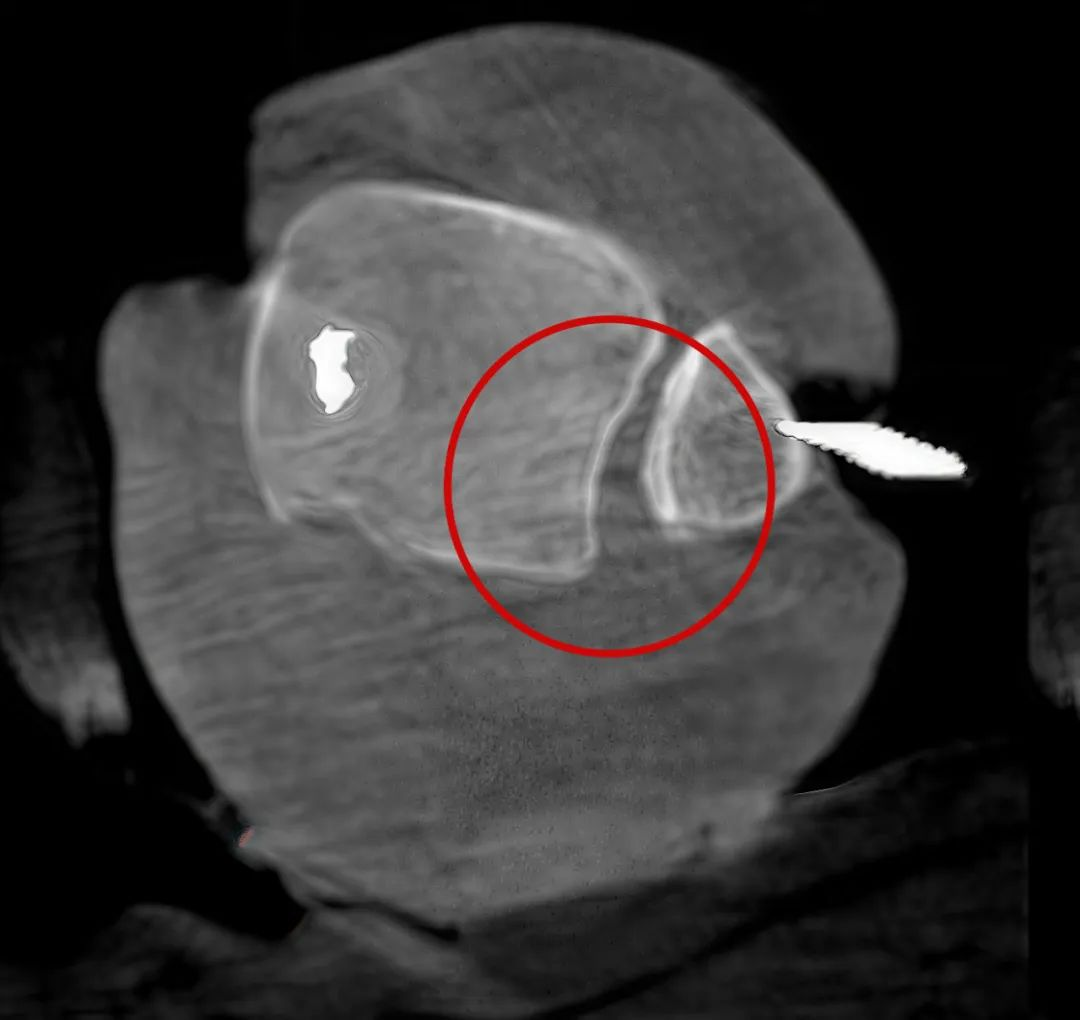

病例2 踝關(guān)節(jié)骨折復(fù)位(31歲)

在踝關(guān)節(jié)骨折復(fù)位手術(shù)中,用三維C可以更好地觀察骨折部位的復(fù)位情況:

正側(cè)位影像觀察脛腓聯(lián)合復(fù)位良好

從三維影像看,復(fù)位欠佳,貼合度不夠